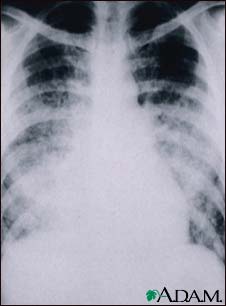

Chickenpox, acute pneumonia - chest X-ray

This chest x-ray shows cloudiness throughout the lungs, caused by acute pneumonia following chickenpox. Pneumonia, as a complication of chickenpox, rarely occurs in children, but occurs in about one-fifth of adults.